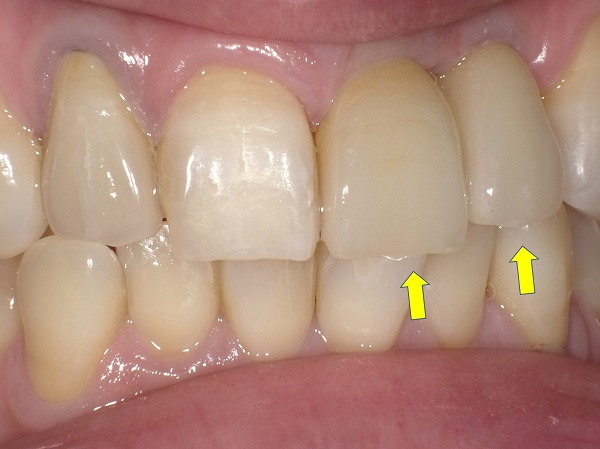

骨幅のない上顎小臼歯部にエクスパンジョンにより Regular size の直径3.7mmインプラントを埋入した症例。

左側上顎第一小臼歯(#24)のエクスパンジョン症例

(40歳代 女性)